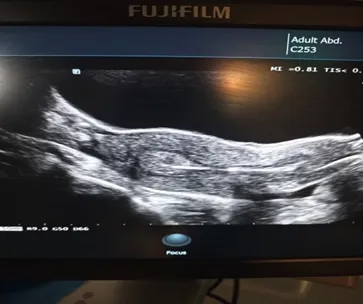

在试管移植过程中,许多准妈妈们都会紧紧的盯着B超屏幕,当白色小光点出现的时候,她们会兴奋的问大夫:

“那是我的胚胎吗?我看到了!”

在这里,很遗憾地告诉大家,那个亮点并不是胚胎本身,而是装载着胚胎的移植导管尖端。

那么,我们看到的亮点是什么?

其实,这个亮点是移植导管前端我们预留的一段空气柱,目的就是让医生在B超下能够精准定位,确保胚胎被放置在子宫内膜最有利于着床的位置。